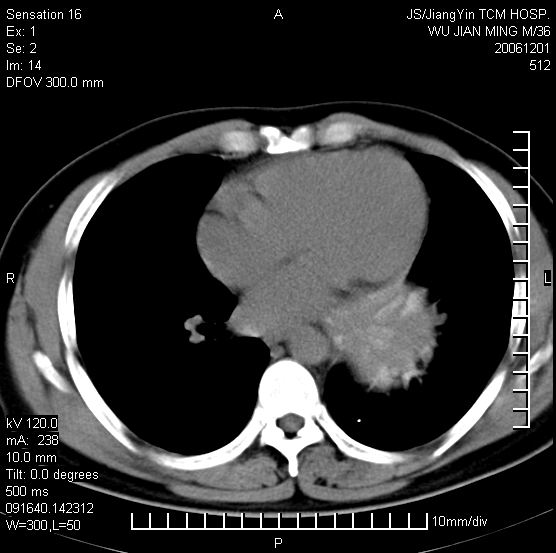

以下是引用dyqct在2006-12-1 21:17:00的发言:[br]左心缘旁及后肋膈窦区见巨大椭圆形混杂密度肿块,周围见大小不等斑片状钙化,内部无强化,周围包膜轻度强化,心脏明显受压变形,即明显占位效应,肿块广基与心包、膈相连。肝、脾内、肝门见多数小结节状钙化影。[br]考虑:1、左心缘旁及后肋膈窦区慢性包裹性胸膜炎(结核性);[br] 2、肝、脾及肝门淋巴结核已钙化。[br]

以下是引用zrs在2006-12-2 17:28:00的发言:[br]肺内、肝脾内虽有钙化,但不支持结核性胸胸膜炎包裹,而支持寄生虫感染![br][br]

以下是引用zyx168在2006-12-2 10:10:00的发言:[br][br]肝脾肺内多发钙化灶